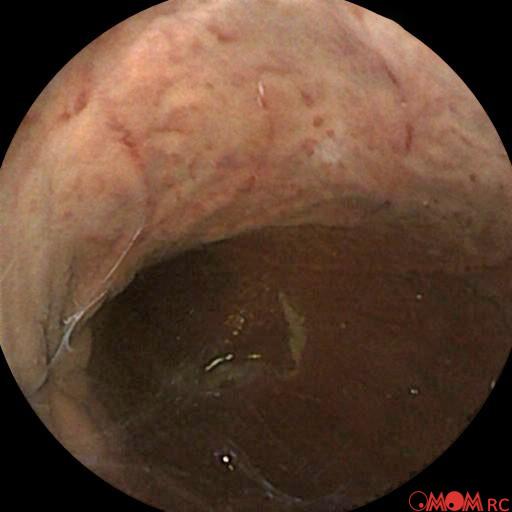

Typical Findings

Polyp Erosion Gastritis Ulcer